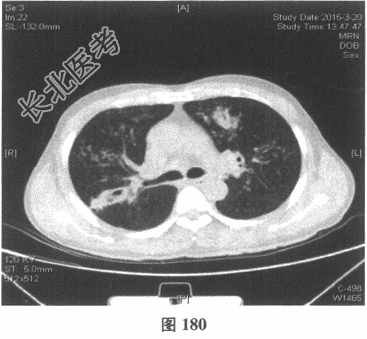

- [材料题] 患者男性,52岁,因间断发热伴咳嗽,咳少许黄痰,无咯血,伴胸闷憋气20余天就诊。体检:体温37.6~38.3℃。既往体健。查体:体温37.6℃,心率83次/分,呼吸20次/分,血压117/64mmHg。神志清,精神可,口唇无发绀;双肺呼吸音粗,可闻及广泛干、湿性啰音,以干啰音为主;心率83次/分,律齐,各瓣膜听诊区未闻及病理性杂音;腹软,无压痛及反跳痛,肠鸣音3次/分,双下肢无水肿。血常规检查:白细胞计数26.32×109/L,中性粒细胞0.846,血红蛋白117g/L,血小板计数1911×109/L;C反应蛋白119.05mg/L。尿常规检查:隐血2(+),蛋白1(+)。痰培养:曲霉菌属,请排除污染。生化全套检查:白蛋白19.6g/L,谷丙转氨酶24.2U/L,谷草转氨酶25.8U/L,γ-谷氨酰基转移酶91.4U/L;尿素氮13.00mmol/L(2.14~7.14mmol/L),肌酐166.8μmol/L(31~132μmol/L);血钾5.6mmol/L。肺部CT见图178~图185。